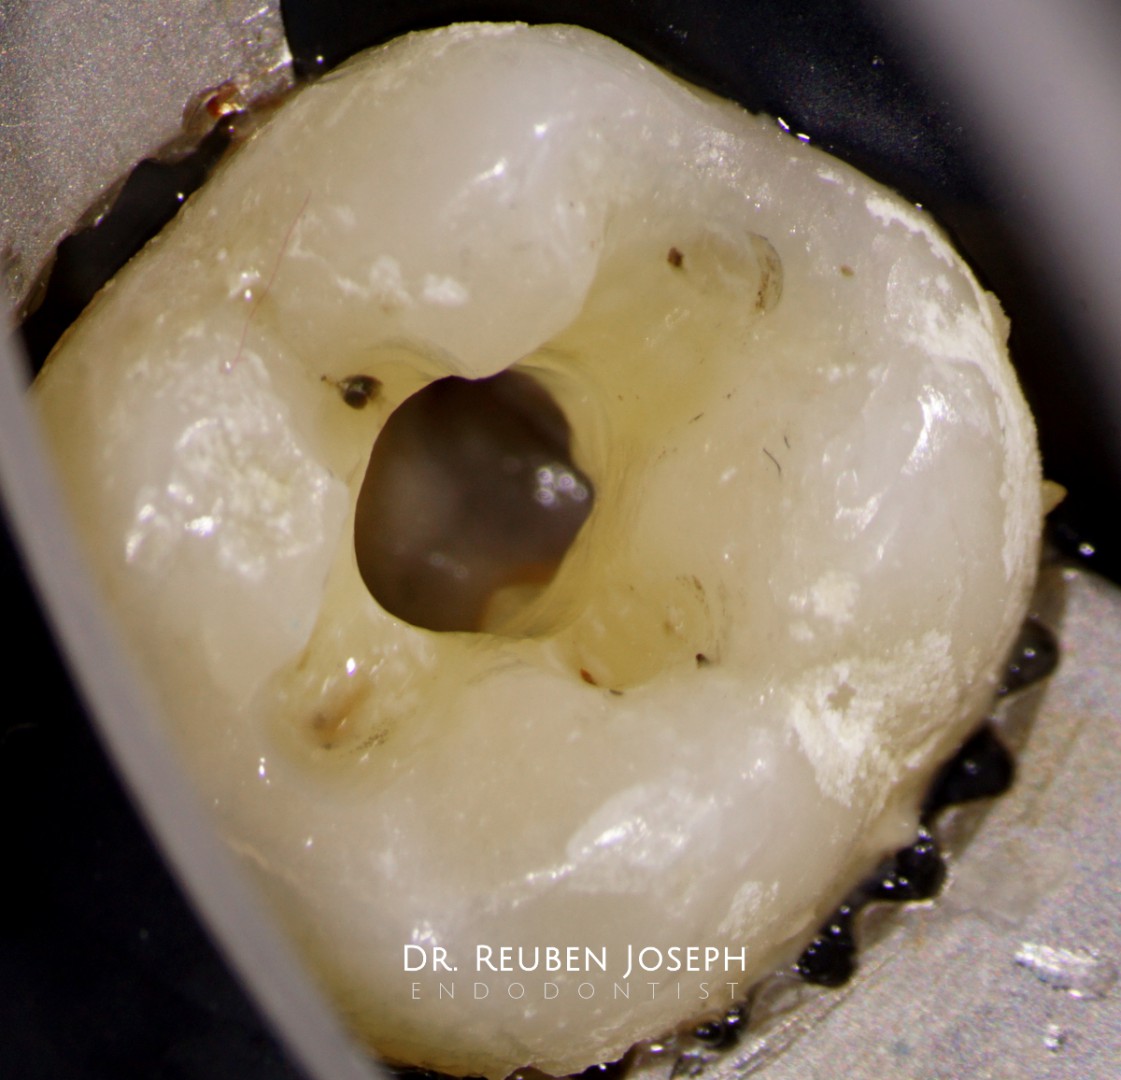

#18 RCT

With this kind of gingiva sinking the whole tooth an indirect post-endo would have been a nightmare (atleast for me) in this case. Orifice directed access done and the carious lesion prepared and restored separately along with the DO in the 19, the cuspal integrity is intact so just the direct composite post the endo.